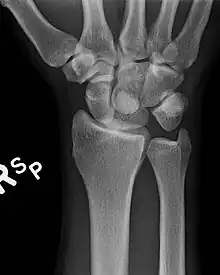

Perilunar dislocation as seen on x-ray.

The lunate bone is the most frequently dislocated carpal bone.